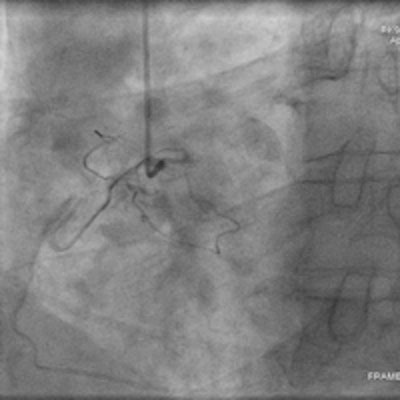

Same patient as above. Left: A conventional left coronary angiogram confirming the CT findings. Right: A conventional right coronary angiogram confirming findings.Since introducing the HD scanner, the radiologists are not only conducting NICE's recommendations, but they're also getting a lot of referrals from cardiologists -- cardiologists send patients with established disease for stent assessment because the radiologists can give more accurate results because of HD.